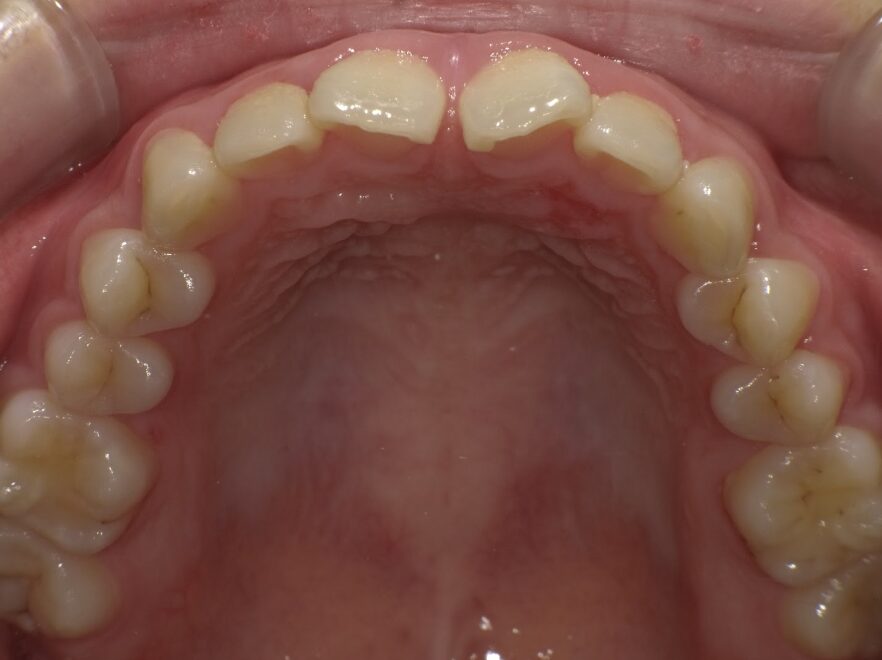

治療前

前歯のすき間が気になるを主訴に当院を受診され、前歯部空隙歯列(歯と歯の間に隙間が空いている状態)・過蓋咬合(上の歯が下の歯を深く覆いかぶさっている状態)・下顎前歯叢生(ガタガタ)を認めました。